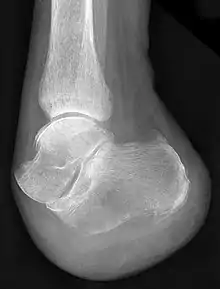

- "Chopart's amputation": Separation of the forefoot at the midtarsal joint.

- "Chopart's fracture-dislocation": Dislocation of the foot through the talonavicular and calcaneocuboid joints along with associated fractures.

- "Chopart's joint" or the transverse tarsal joint: Articulation between the hindfoot and the midfoot.